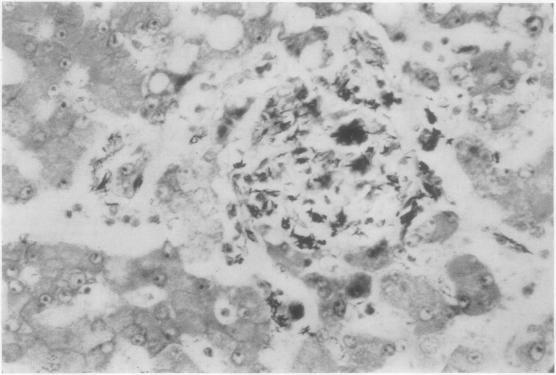

Non-reactive tuberculosis.

J Clin Pathol. 1954 Aug;7(3):216-25. doi: 10.1136/jcp.7.3.216.